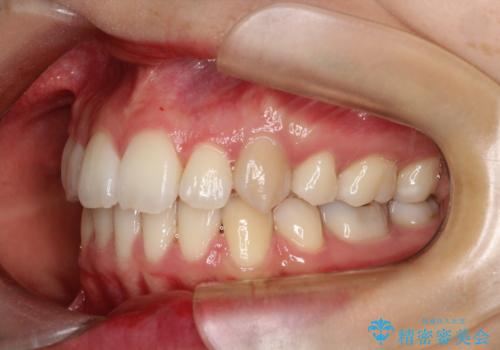

重度のガタガタ ハーフリンガルによる目立たない抜歯矯正

歯並びがコンプレックスで歯を見せて笑うことができなかったとのことですが、歯並びがよくなり、口元を気にせずに笑えるようになったと喜んでいただきました。